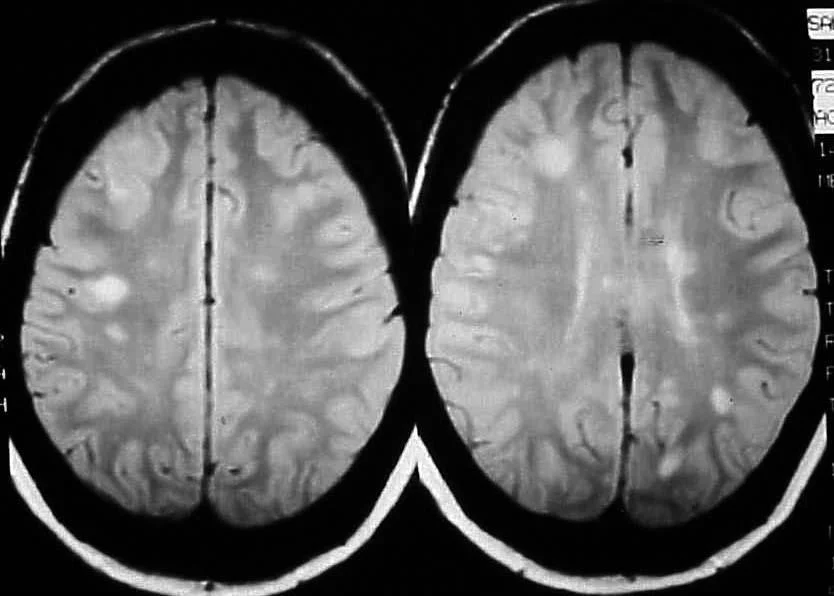

The most commonly associated cause of inflammatory optic neuropathy is demyelinating optic neuritis secondary to multiple sclerosis (MS).

The initial inflammatory cascade leads to phagocytosis of the myelin sheath.

As a result, gliotic tissue is laid down in place of missing myelin.

This substitutive tissue lacks the conduction properties of myelin, leading to nerve impulse interruption.